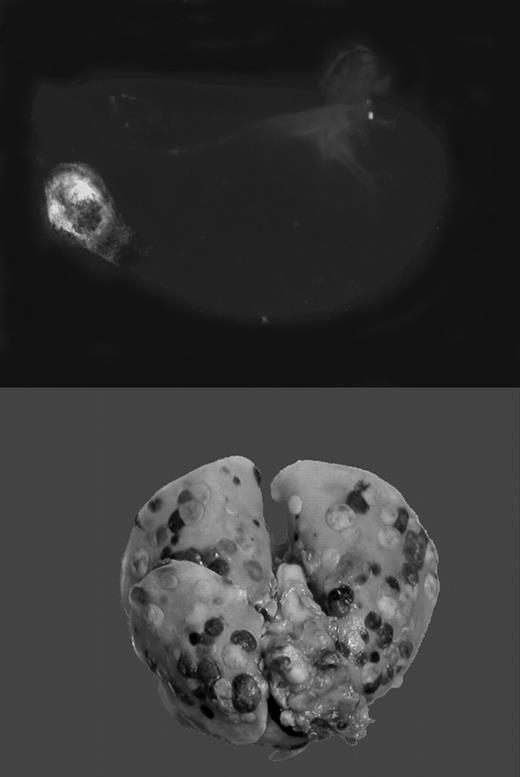

Tumor cells travel through blood or lymphatic vessels to secondary organs, where they exit the vascular compartment to form metastases. This route of tumor dissemination through the bloodstream has been termed hematogenous metastasis. The level of tumor-associated procoagulant activity correlates directly with metastatic potential, and forced expression of the initiator of blood coagulation, tissue factor (TF), is sufficient to confer metastatic potential onto tumor cells.1 In animal models, metastasis can be effectively suppressed by genetic disruption or pharmacologic inhibition of the coagulation system or platelet activity. Using genetically altered mice lacking fibrinogen, Palumbo and colleagues previously demonstrated that absence of fibrinogen markedly reduces the formation of pulmonary and lymph node metastases, without affecting growth of the primary tumor.2 Recent work by Camerer and colleagues3 confirms this finding, and, in addition, showed that platelets are also necessary for successful hematogenous metastasis. Importantly, attenuating platelet responsiveness to thrombin suppressed metastasis to a similar extent as the complete absence of platelets, or the lack of fibrinogen. Together, these studies clearly established that metastasis of circulating tumor cells requires TF-initiated coagulation on the surface of tumor cells, which promotes thrombin generation, fibrin formation, and platelet aggregation. However, it remained obscure how this chain of events translates into an enhancement of metastasis.FIG1

Gαq deficiency dramatically diminishes the metastatic potential of circulating tumor cells. See the complete figure in the article beginning on page 178.

Gαq deficiency dramatically diminishes the metastatic potential of circulating tumor cells. See the complete figure in the article beginning on page 178.

The current article by Palumbo and colleagues follows an earlier lead suggesting that platelet aggregation around procoagulant tumor cells shields these cells from attack by cytolytic natural killer (NK) cells.4 NK cells eliminate the vast majority of circulating tumor cells, and NK cell elimination or inhibition results in greatly exaggerated metastasis. NK cell–mediated tumor killing requires direct contact with the target cell, possibly via transcellular interleukin 15 presentation.5 The acquisition of a platelet cloak around the tumor cell could in theory prevent such interactions, and allow the tumor cell to escape the surveillance by cells of the innate immune system. Palumbo et al test this hypothesis by employing fibrinogen-deficient mice, mice with aggregation-defective platelets (lacking the signal transducer Gαq), and mice with defective NK cell function. They demonstrate that the metastasis-enhancing effect of fibrinogen and platelets is completely abolished in the absence of NK cells, thus providing an independent and convincing experimental verification of the hypothesis proposed by Nieswandt and colleagues.4 It remains to be shown whether platelets protect tumor cells indeed simply by providing a physical barrier, or whether platelets modulate NK function in some additional way. The current article by Palumbo et al also establishes an experimental paradigm in which NK-independent mechanisms linking tumor metastasis and hemostasis can be addressed. Insight into the role of platelets in the adhesion of tumor cells to endothelium, the effects of thrombin on mobilization of tumor cells, and the role of coagulation, platelets, and receptors in the extravasation/diapedesis of tumor cells is sure to emerge from further analysis of these pathways in NK-deficient mice.